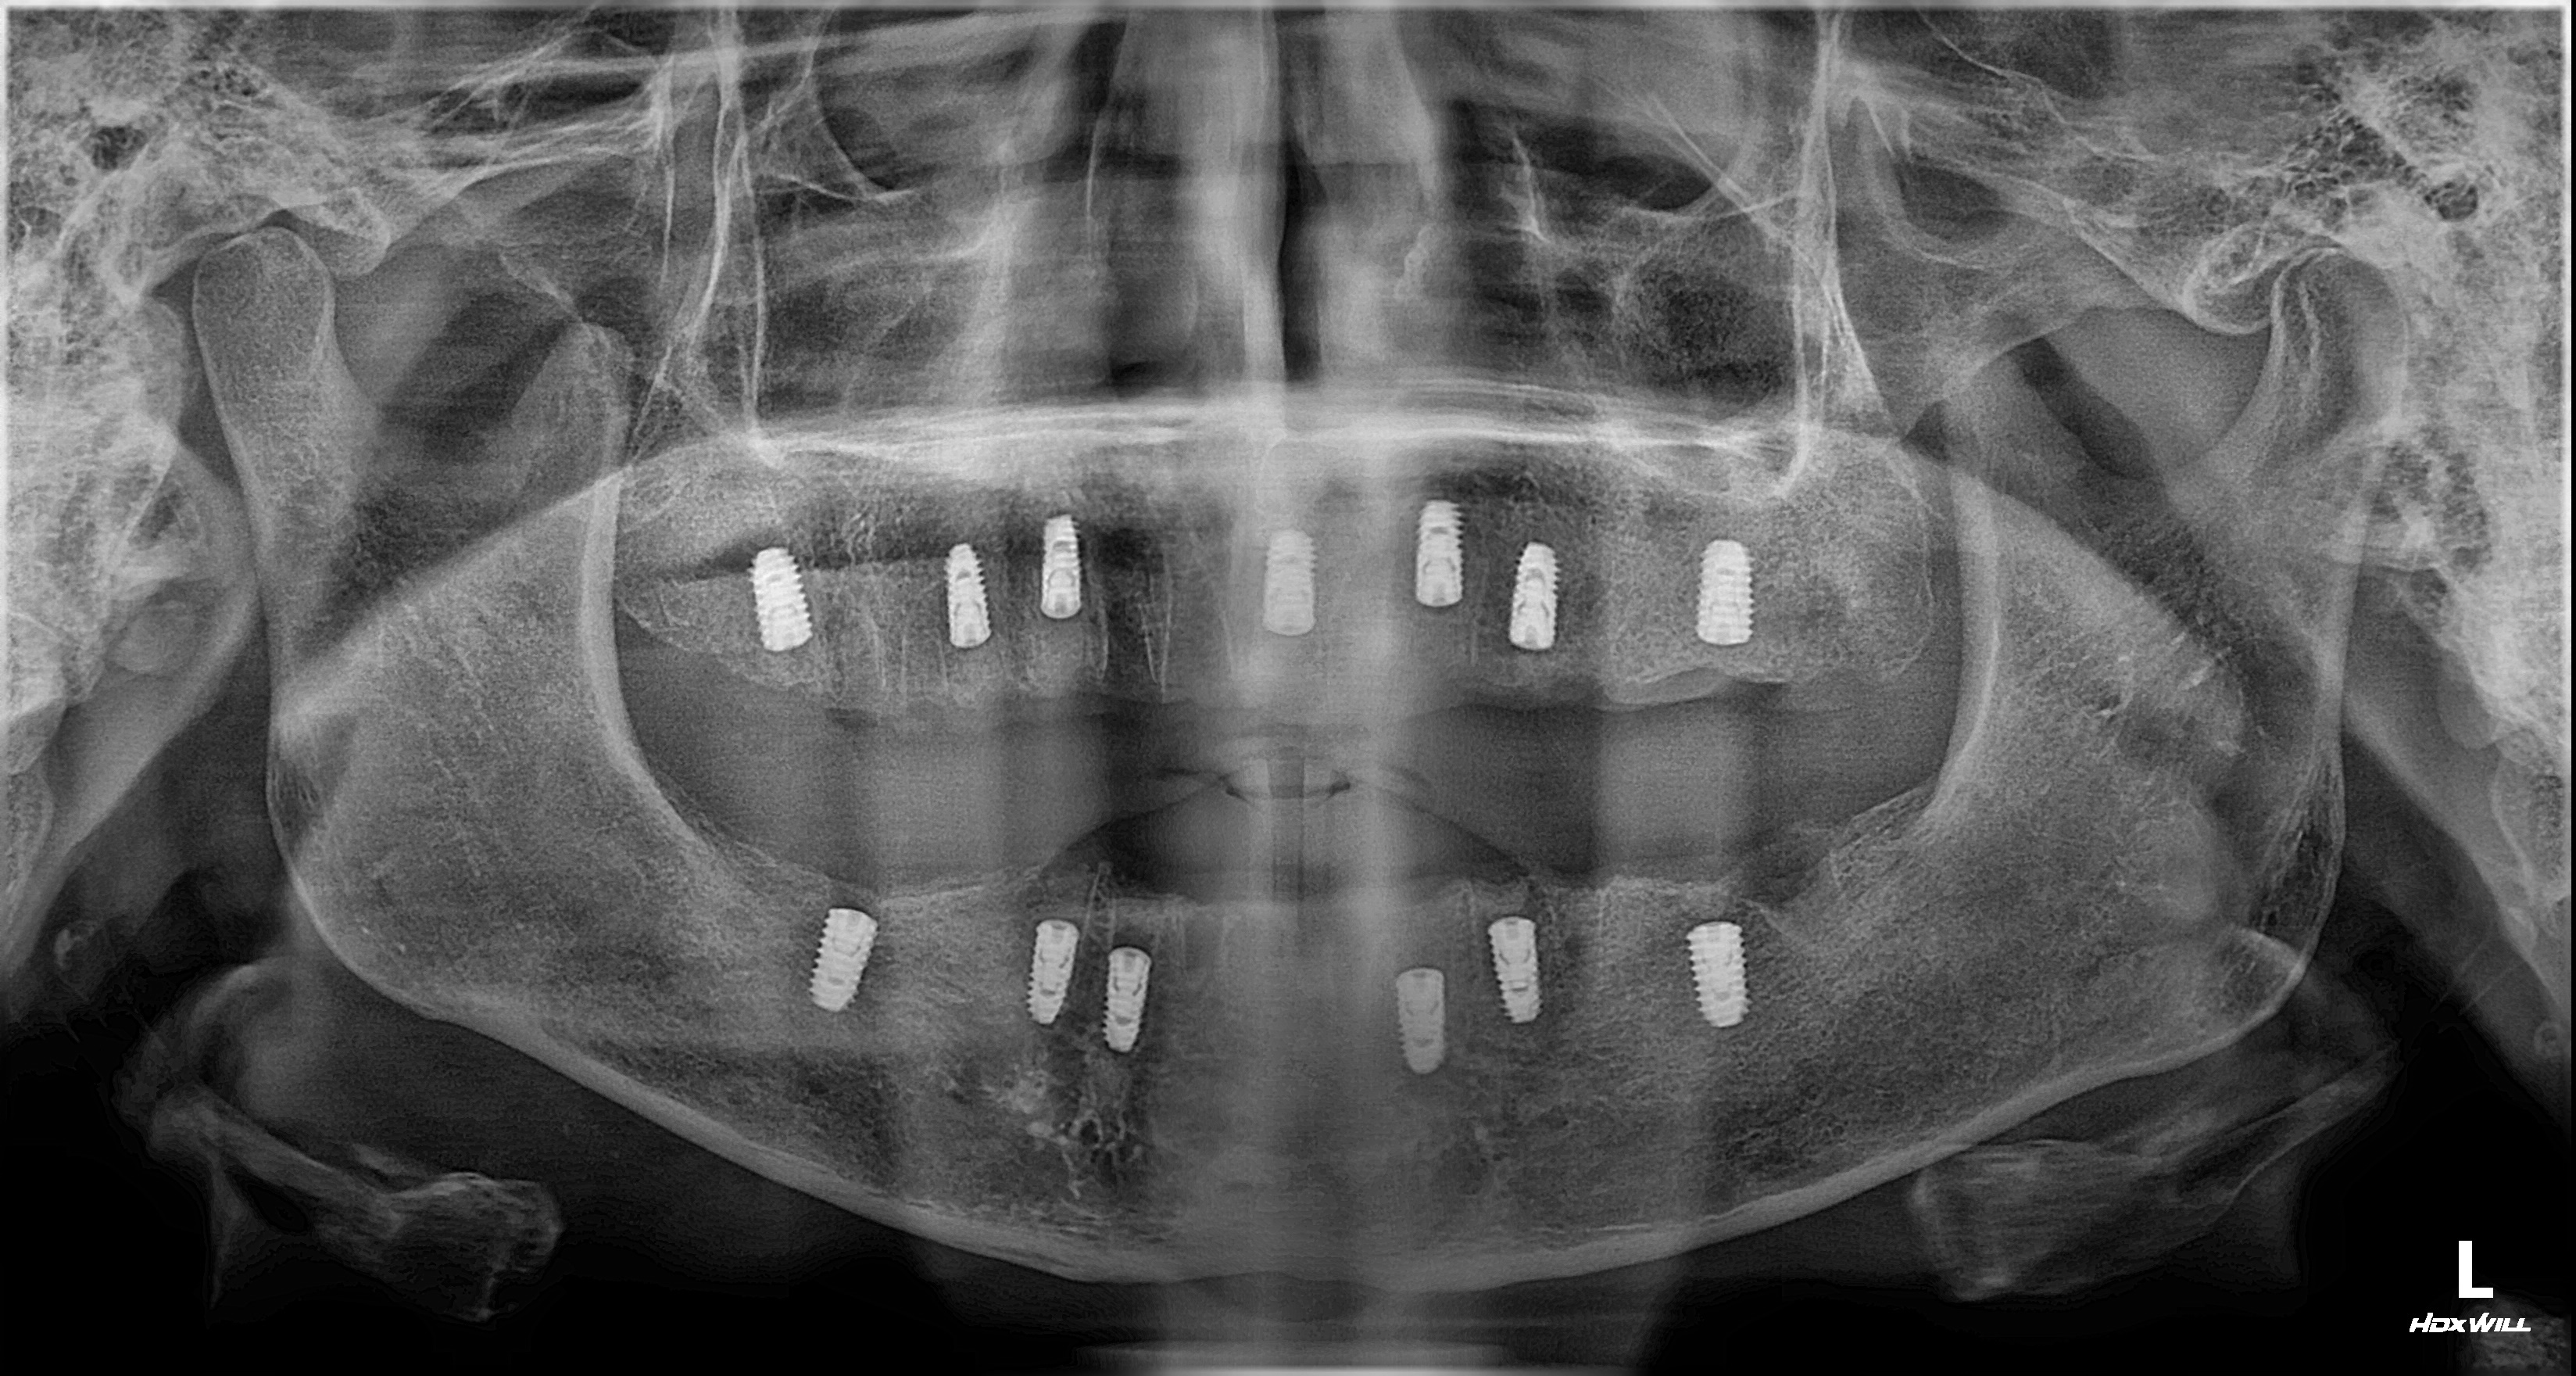

촬영일시: 2025.05.27